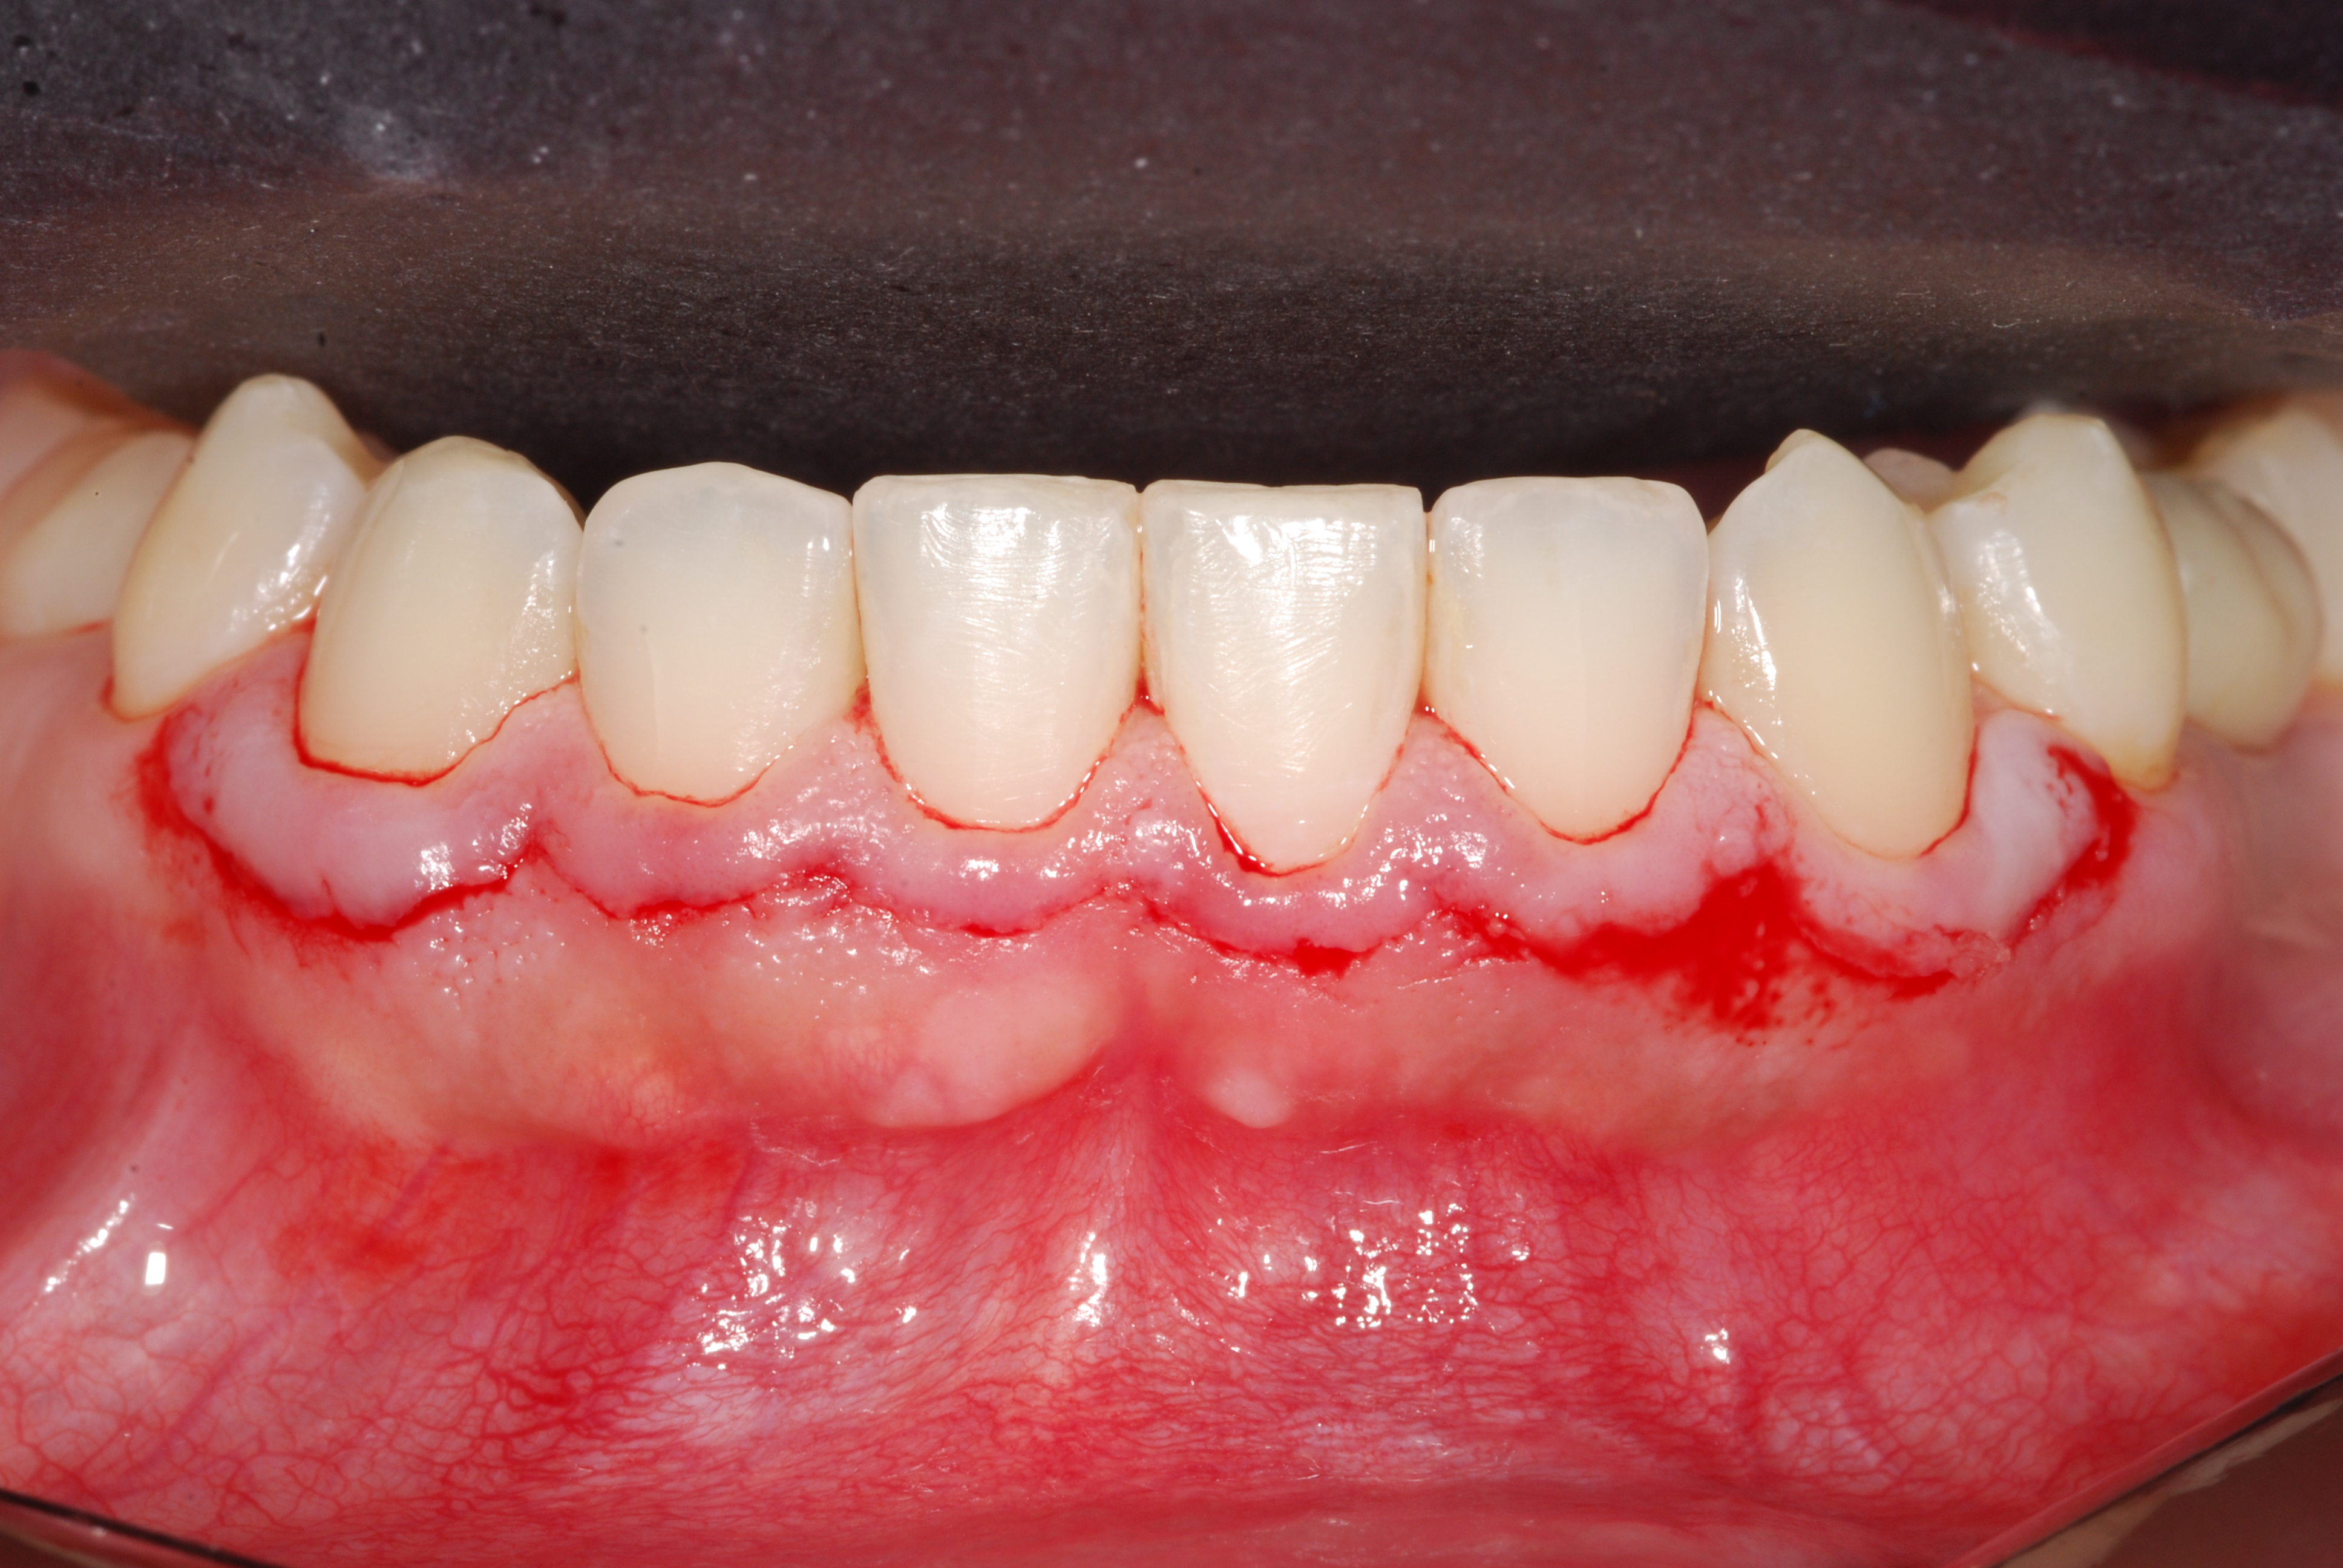

The presence of diastema, between anterior teeth, distorts a pleasing smile by concentrating the observer’s attention on the spaces. The patient’s needs and expectations must be considered in the process of treatment planning to ensure satisfaction with the treatment outcomes. There are many forms of therapy that can be used for diastema closure. A carefully developed diagnosis, which includes a determination of the causal elements and advanced treatment planning, allows the most appropriate treatment to be selected for each case. The aim of this paper is present a multidisciplinary approach as a solution to multiple diastemas in the anterior region using gingival tissue recontouring and direct adhesive restorations, with minimum wear of the dental structure, after the orthodontic intervention discussing the minimal intervention to obtain imperceptive and aesthetic final restoration. Thirty-six months after the treatment was carried out, the final aesthetic was maintained with all dental element details and gingival tissue harmony, without recurrence of periodontal pockets and the preservation of the tooth color and shape.